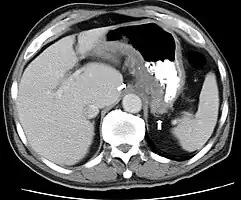

CT and MRI scans are useful for evaluating the small bowel with enteroclysis protocols.[138] They are also useful for looking for intra-abdominal complications of Crohn's disease, such as abscesses, small bowel obstructions, or fistulae.[139] Magnetic resonance imaging (MRI) is another option for imaging the small bowel as well as looking for complications, though it is more expensive and less readily available.[140] MRI techniques such as diffusion-weighted imaging and high-resolution imaging are more sensitive in detecting ulceration and inflammation compared to CT.[141][142]